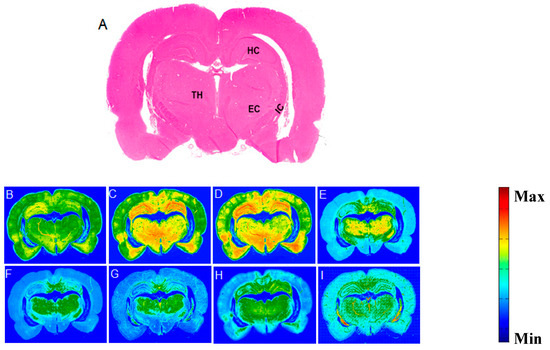

Figure 3A is an example of the H&E image of a caudal brain section that represented three regions of interest: HC, TH, and EC. Figure 3B shows the corresponding FTIR image from these sub-fields. Figure 3C–I represent the biochemical components of this caudal brain section. The hippocampus H&E stain (Figure 4A), clearly shows the cyto-architecture of this organ. The figure revealed that the hippocampus has densely-packed neurons in the cornu ammonis (CA) sub-fields and the dentate gyrus (DG), and a smooth, less-dense upper region of the avleus (AV). The spectroscopic results (Figure 4B) indicate that there is a similarity between the CA and DG spectra, in contrast with the AV spectrum. The main differences were observed in the following spectral bands: (a) In the AV’s FTIR spectrum, the intensity of the νs(CH2), νas(CH2), and the ν(C=O) ester bands showed stronger absorption than the CA and DG spectra, indicating that the AV is enriched in lipid content. (b) The olefinic structure olefinic=CH band at 3012 was stronger in the CA and DG spectra than the AV spectrum. (c) The band at 2955 cm−1 which arose from the νas(CH3), was stronger in the CA and the dentate gyrus (DG) spectra than the AV spectrum. (d) The amide I and amid II bands exhibited a higher absorption in the in the CA and the DG spectra, in comparison to the AV spectrum. (e) The spectra revealed that the CA and DG regions yielded a low lipid-intensity, while the CH2 spectral bands had a strong absorption, at the white matter location, which surrounded the entire hippocampus. These intense CH2 bands were due to the high lipid-bilayer concentration in the white matter.

Figure 3. (A) H&E staining section of the caudal brain (Bregma −4.36 mm) showing four regions of interest (ROI): HC, TH, IC, and EC. (B) Corresponding FTIR image. (CI) Representative images of the biochemical components—Amide I, Amide II, CH3 asymmetric, CH2 symmetric, CH2 asymmetric, Olefin, and Ester, respectively.